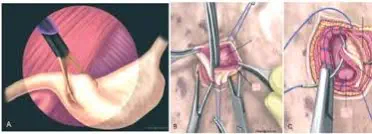

Gastropexie durch Laparotomie:

Hier wird ein größerer Bauchschnitt vorgenommen, nach dem der Chirurg die Magenwand an die Bauchdecke näht.

Gastropexie durch Mini-Laparotomie mit Unterstützung der Laparoskopie:

Unter dem Blick einer Kamera im Bauchraum wird die Magenwand mit einer Gewebezange gefasst und durch einen kleinen Bauchschnitt in der Flanke herausgezogen.

Danach wird die Magenwand in die Bauchwunde eingenäht und die Wunde wieder verschlossen.

Gastropexie nur per Laparoskopie:

Dabei wird die Magenwand mit Hilfe einer Kamera und weiterer Instrumente vollständig von innen an die Bauchdecke genäht.

Laparoskopisch assistierte Gastropexie mit Mini-Laparotomie